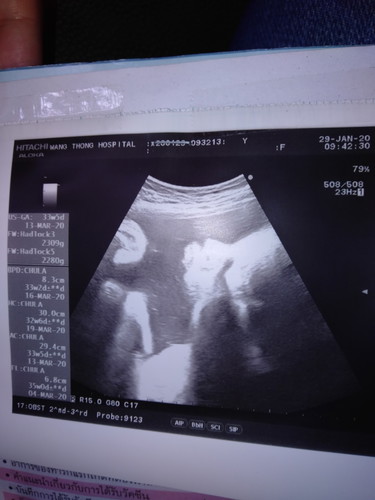

แม่ๆช่วยดูน่อยค่ะว่าผู้หญิงหรือผู้ชาย

ไม่ชัดค่ะ ดูไม่ออก

ดูไม่เห็นเลยค่ะ 😂

ไม่ชัดเลยค่ะ

ดูไม่ออกค่ะ